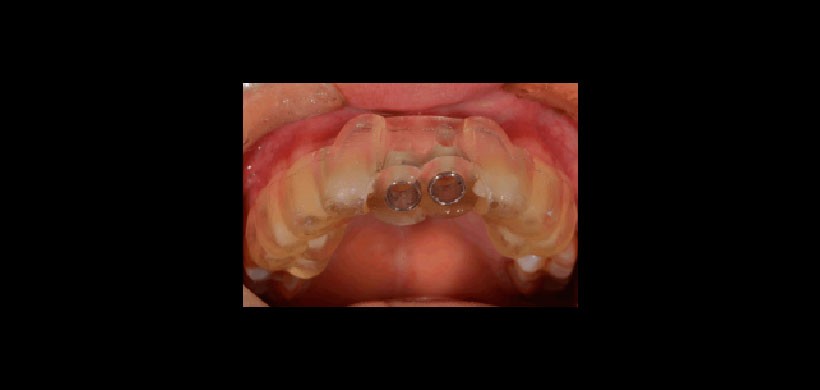

Fig 3. Guía quirúrgica dentosoportada, brinda mayor estabilidad.